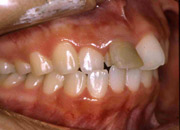

欠損した奥歯をインプラントで修復すれば、強度と安定性が得られ、好きなものを何でも食べられるようになります。また顎骨も顔の外観も保たれます。

奥歯が3本欠損しています。この場合の治療法の1つとして、固定ブリッジを装着することです。 |